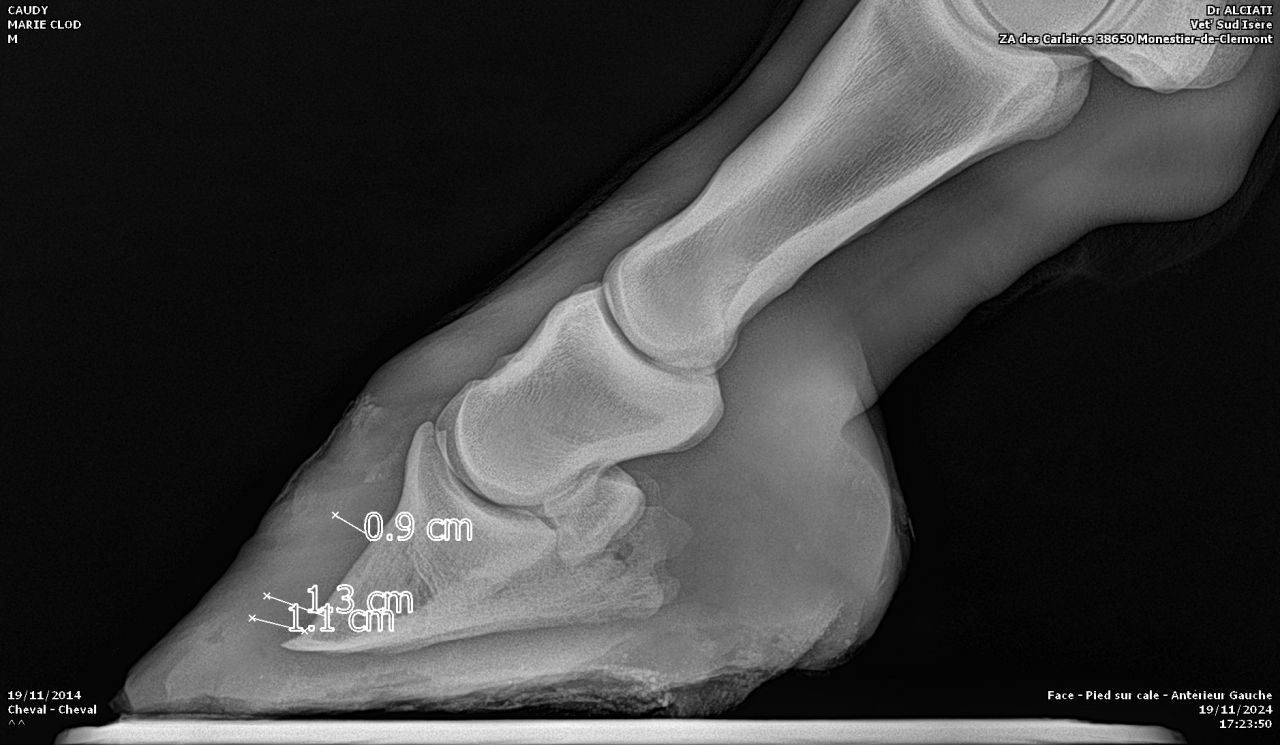

| Dire merci | Je fais un sujet à part pour donner des nouvelles ![]() J’ai fait passer un autre véto pour un 2ème avis. Au début il pensait à un abcès très profond, emplacement détecté avec la pince à sonder. Il a ensuite fait des radios : si j’ai bien compris, la 3ème phalange appuie sur la sole Il y a également de l’arthrose ... Le traitement pour le moment : anti inflammatoires et hipposandales en attendant de pouvoir referrer, et changer de maréchal ferrant. Apparemment il existerait un traitement au laser, le véto va se renseigner. Cody a fait une fourbure l’année dernière, des radios ont été faites à ce moment. J’ai aussi refait des radios de contrôle cette année, il restait une légère bascule de P3. |

| Dire merci | Radios de mai 2023![]() ![]() Radios de juillet 2023 ![]() ![]() Radios d'août 2024 ![]() ![]() |

| Dire merci | Il y a quand même de jolies bascules, il doit pas être bien c'est sûre. Les degrés de bascule t'ont été donnés? Pour moi il y a urgence à trouver un bon maréchal, qui va travailler avec les radios, mais ça va mettre plusieurs mois à "rentrer dans l'ordre" si pas d'autres crises inflammatoires et nouvelles bascules, ça se compte en plusieurs mois voir année. Et malheureusement une surveillance constante. |

| Dire merci | J'ai eu le collègue du véto au téléphone : pas de risque immédiat que la phalange perce la sole il reste 1 cm. La 3ème phalange appuie sur la sole, il y a nécrose. La pointe ne risque pas de casser. Je viens de commander 2 hipposandales Cloud. Il faut que je trouve quelqu'un pour déferrer Cody et éventuellement parer l’autre antérieur. Message édité le 22/11/24 à 20:31 |

DéconnectéDire merci | pas de risque immédiat que la phalange perce la sole il reste 1 cm. Bien optimiste ce véto car tant que le pied reste ferré donc en support périphérique plutôt que le poids soit porté par toute la sole une descente peut aller très vite. C'est une logique mécanique. |

| Dire merci | Voici les dernières radios :![]() ![]() ![]() |